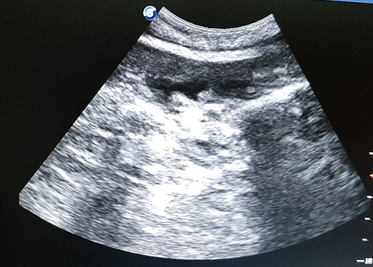

Canine pyometra is one of the most frequent reproductive organ disorders in reported in intact female dogs, particularly during the diestrus phase of estrus cycle and progesterone dominant uterus.1 Pyometra is accumulation of exudates within the uterine lumen, typically occurring during or immediately after a period of progesterone dominance. Clinical signs associated with this kind of disorder include lethargy, anorexia, polydipsia, polyuria, vomiting and unusual vaginal discharge (Kuplulu et al., 2009).2 The most accurate method of diagnosing pyometra in canines is ultrasonography.3 Both qualitative and quantitative examination is possible in diagnosing pyometra.4 In case of Pyometra, uterus will appear as distended and anechoic sacs are visualized due to pus accumulation. The advantage of ultrasonography is that it can detect the intrauterine fluid even in smaller quantity and also detect the abnormal changes in the ovaries and uterine tissue.5 Depending on the extent of uterine involvement, ultrasonographic features of pyometra may vary, the areas of uterine involvement may appear as hypoechoic or anechoic areas like if moderate involvement is there, it will appear as hypoechoic, roughly round structure ventral to ventro-lateral to the anechoic urinary bladder in transverse section. On ultrasound examination, cystic endometrial hyperplasia (CEH), which precedes pyometra, appear as small, cyst like fluid-filled regions within the endometrium (Figure 1). Similarly, transabdominal ultrasonography is effective way in diagnosing closed type of pyometra. A characteristic multiple anechoic sacculations with changes in the uterine wall thickness is visible as depicted in Figures 2–4. Therefore, ultrasound can be used as non-invasive and rapid diagnostic technique to detect the uterine pathologies like CEH and pyometra.6–10

Figure 2 Ultrasonographic view of uterus showing thickened uterine wall and fluid accumulation in the lumen.